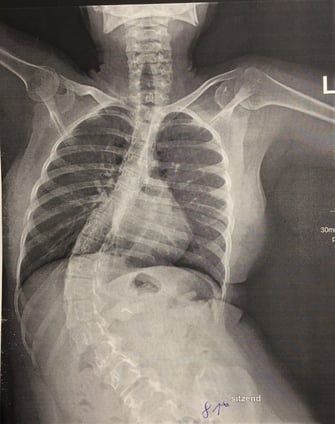

Es werden Fotos und Röntgenaufnahmen gezeigt.

Es folgen eine lange Reihe von sehr eindrucksvollen Fotos, Röntgenbilder, Vorher-Nachher-Bilder.

Ausgangsituation

nach Korrektur